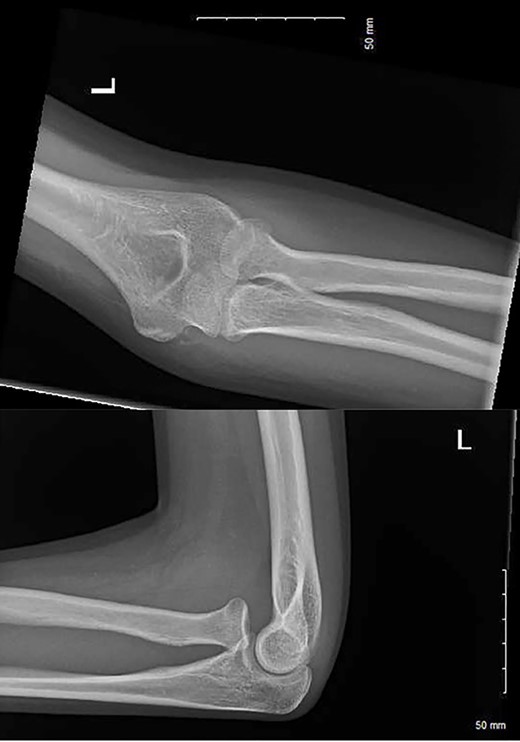

A 15-year-old right-hand-dominant female fell from her horse onto an outstretched left hand (elbow extended, forearm pronated) at an equestrian event (Video 1). The patient immediately attended the emergency department with pain and significant swelling over the medial and lateral aspect of the elbow. Radiographs were performed (Fig. 1) and an undisplaced radial neck fracture was identified. As per guidance for non-displaced radial neck fractures, the patient was discharged with a broad-arm sling and a follow-up appointment was scheduled in VFC. At VFC, the patient was discharged with a plan to mobilize as the pain allows, avoid lifting for 2 months and to return if experiencing limitation in the range of movement.

AP and lateral radiographs of the injury at first presentation to the emergency department.